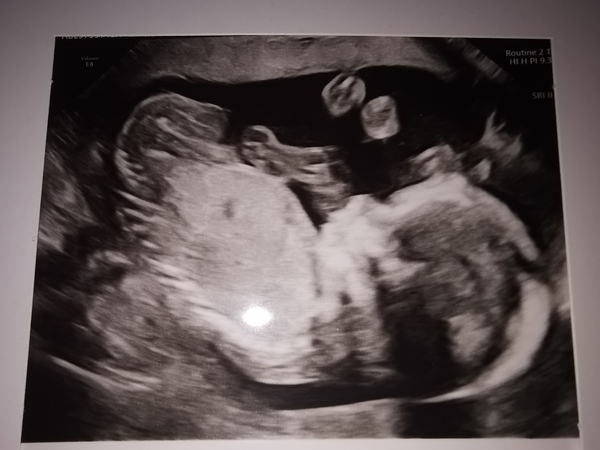

20 week anomaly scan this morning is over and done with thank goodness and all is looking well so far 😊 weirdly after having been put back 1 day at the dating scan from 13+2 to 13+1, he's now shot ahead and is measuring 21 weeks exactly at 20+1 today so hopefully that explains why I've been feeling so rubbish and have had so much discomfort these past few weeks!

@SamoyedFan123 congratulations! massive milestone! He's looking gorgeous. Can you feel the movements more now that he's bigger?